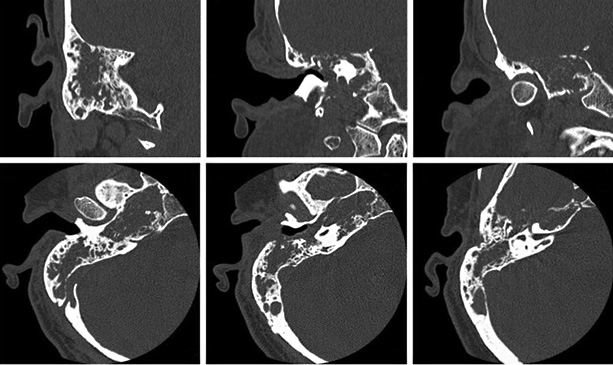

- Tomografía computada (TAC) o imagen por Resonancia magnética (RM) que permite a los médicos ver el cerebro, el oído medio y otras estructuras dentro de su cabeza. Estos exámenes descartan tumores y otros problemas que pueden causar síntomas similares a los del síndrome de Ménière.